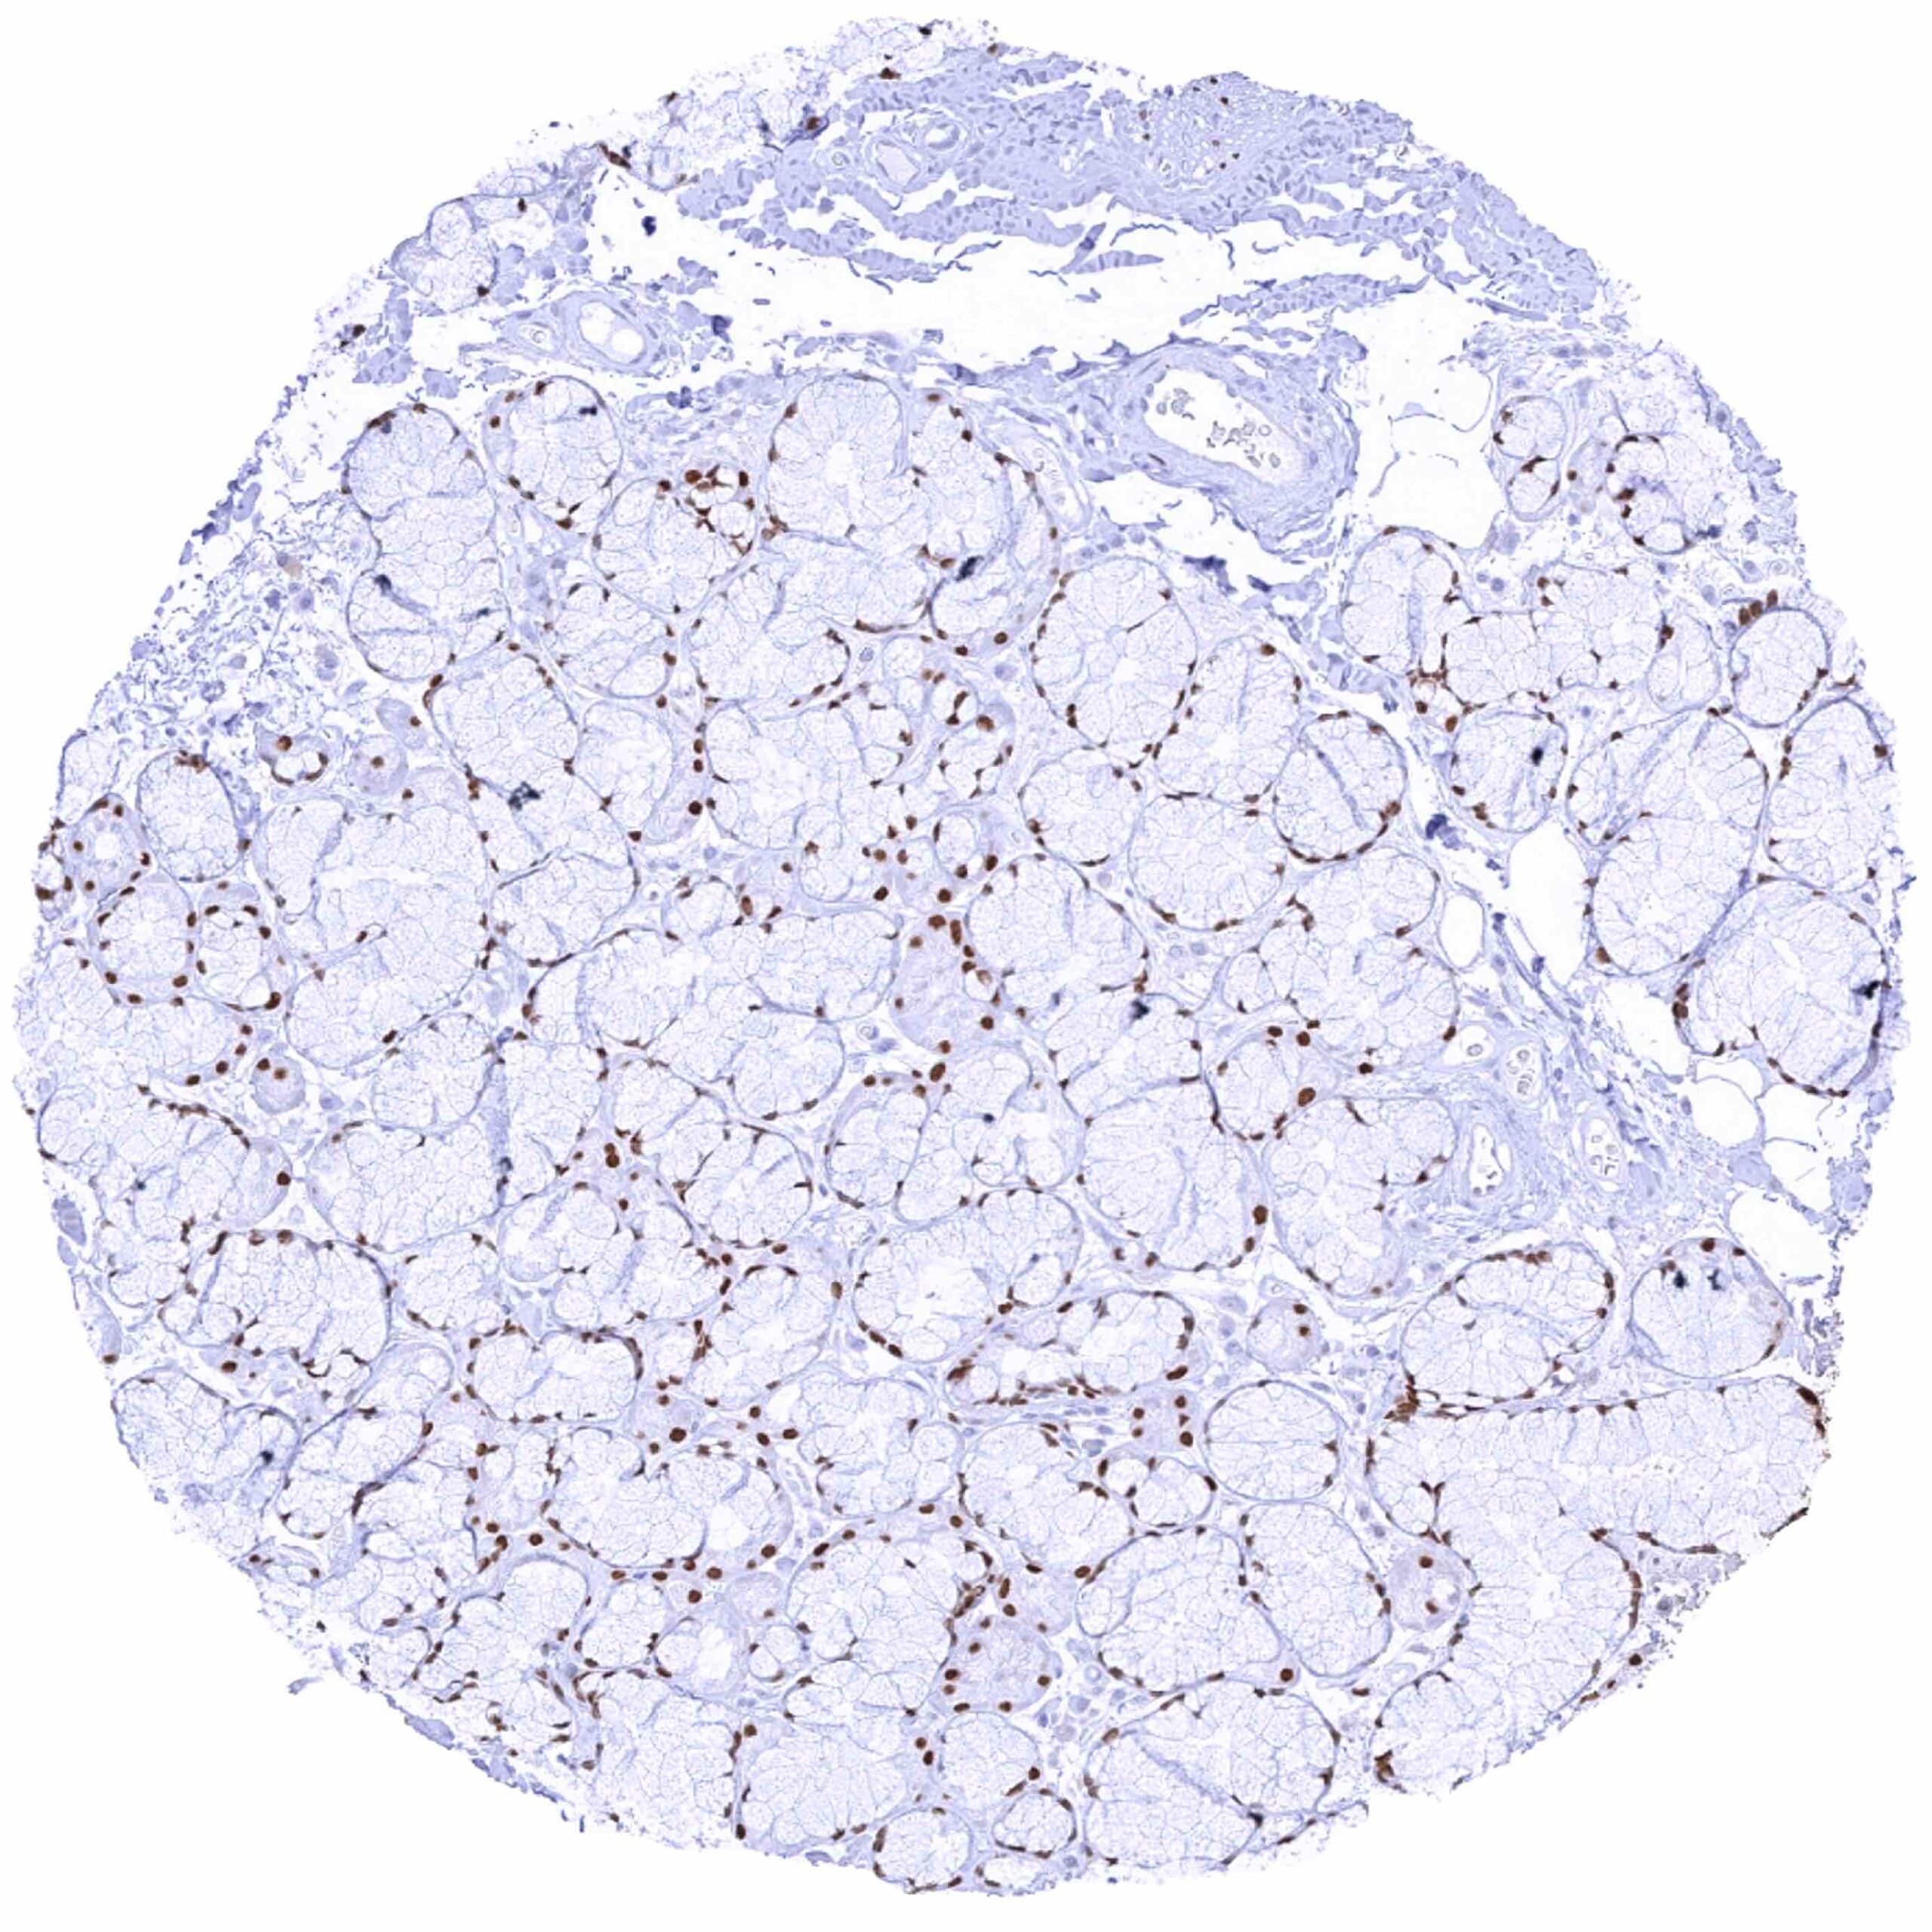

Testis – Weak to moderate SOX2 positivity of spermatocytes